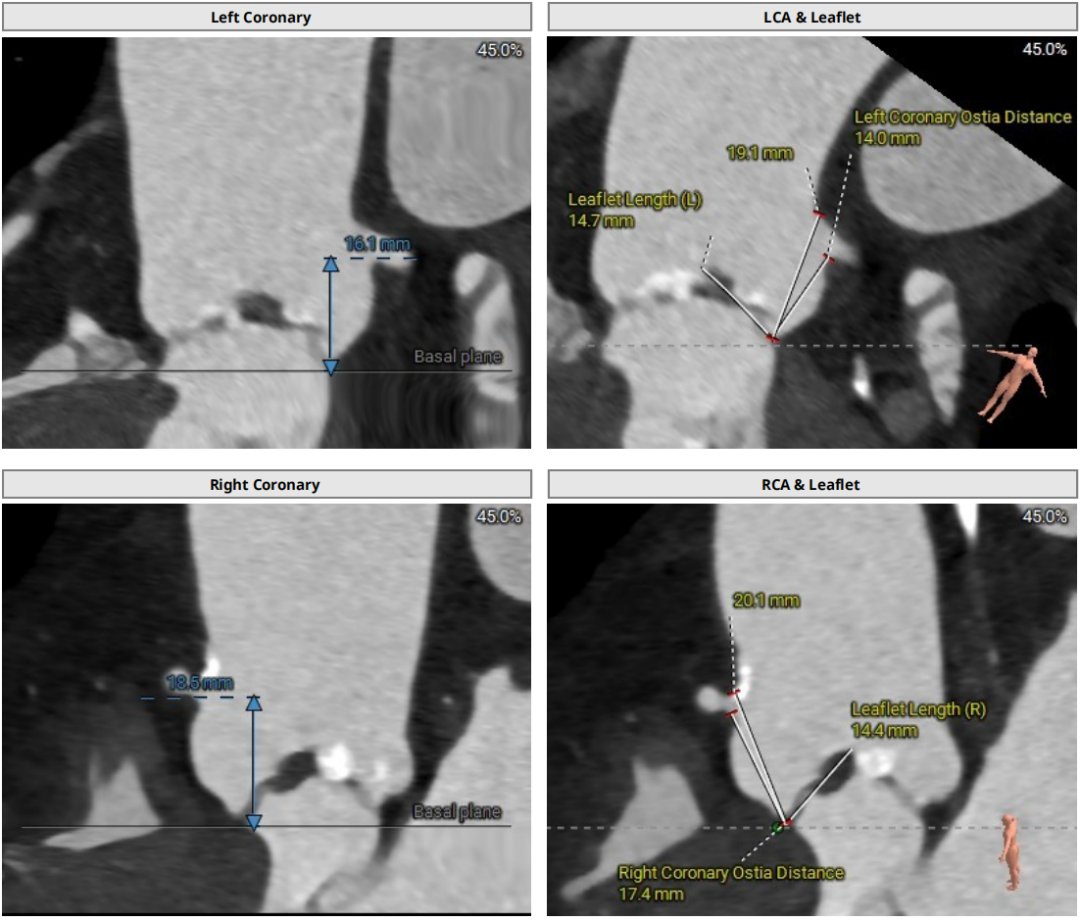

冠脉风险评估

左冠高度:16.1mm

右冠高度:18.5mm

左右冠高度可,瓣叶长度可,综合评估左右冠阻挡风险低。